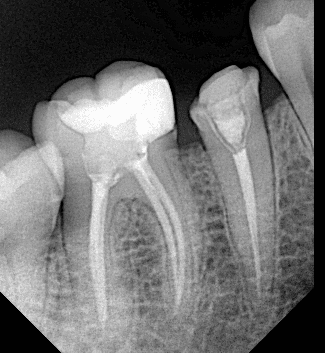

Initial x ray

After preparing the tooth

Final x ray